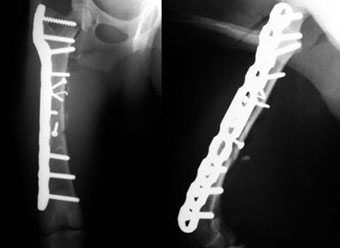

体重10kgの犬の大腿骨近位粉砕骨折。

一見、ただの斜骨折に見えますが、実際には、近位側は6つの骨片に分離しており、根本近くまでひびが入っていました。

骨片をラグスクリューと細ピンで近位側骨にまとめてからニュートラリゼーションプレート法で固定しました。

写真上段: 手術前

写真下段: 手術後

プレート手術では、骨のカーブに合わせてプレートを曲げるベンディングという作業を行います。この症例の術後写真では、大腿骨のほぼ全長にわたってプレートをかけているので、プレートがベンディングされている様子がよくわかります。